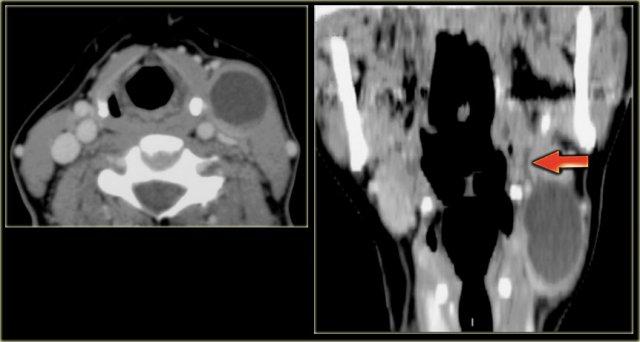

U lympho (2)

Bên trái là hình ảnh của một phụ nữ 67 tuổi có tiền sử u lympho không Hodgkin.

Bệnh nhân gần đây phát hiện sưng nề ở bên trái cổ.

Bước 1

Hình ảnh CT tại mức dây thanh âm thật cho thấy một khối rõ ràng nằm trong khoang cổ sau.

Bước 2

Khối có bờ rõ và đồng tỷ trọng với cơ.

Hình ảnh tái tạo mặt phẳng coronal cho thấy khối có hình dạng thuôn dài, kéo dài về phía nách theo đường đi của đám rối thần kinh cổ-cánh tay.

Tiếp tục xem các hình ảnh MRI.

Tổn thương xuất phát từ lỗ liên hợp thần kinh bên trái và phát triển dọc theo đường đi của đám rối thần kinh cánh tay (mũi tên đỏ).

Thực chất, chúng ta đang quan sát thấy hình ảnh đám rối thần kinh bị dày lên rõ rệt.

Bước 3

Đặc điểm hình ảnh học xác nhận nguồn gốc thần kinh của khối.

Kết hợp với tiền sử bệnh, chẩn đoán cuối cùng là thâm nhiễm lan tỏa đám rối thần kinh cánh tay trái do u lympho không Hodgkin tái phát.